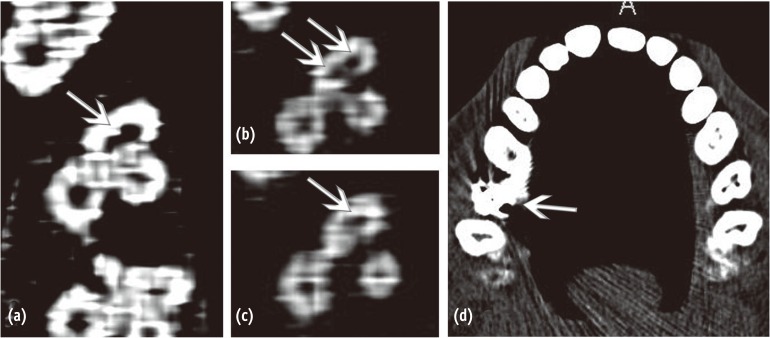

Subsequent to anesthesia and rubber dam isolation, access cavity preparation was initiated and the mesiobuccal, distobuccal, and palatal canals were located. Anticipating the presence of extra canals, further exploration was carried out deliberately and two sticky points were located. This led to finding of two additional canals in the mesiobuccal root on the line connecting the mesiobuccal and palatal canal orifice (Figure 1). Magnifying loupes (2.5X, ST250, STAC Dental Instruments Inc., Brampton, Canada), a DG 16 endodontic explorer, and sodium hypochlorite were the adjuncts used to locate the canals. After locating the orifices, an attempt was made to understand the internal anatomy of the mesiobuccal root using K files and intraoral periapical radiographs. While negotiating the canals individually in the mesiobuccal root, there was no hindrance in the movement of the #10 K file in any of the three canals. However, simultaneous insertion posed obstruction in the vertical movement of the files in the 2 extra canals. The above finding raised an element of doubt regarding the configuration of the canals. Intraoral periapical radiographs were taken from three different horizontal angulations (Figures 2a, 2b and 2c). However, all of the radiographs suffered from overlapping of the endodontic files radiopacity. Only a mesially angulated radiograph revealed limited information on where files associated with the second and third mesiobuccal canals were seen to be meeting in the middle third of the root approximately and continue to merge with the file in first mesiobuccal canal (Figure 2b). To avoid any missed canals, and for better understanding of the tooth's internal anatomy, a MDCT (Brilliance CT 64-channel, Philips Healthcare, Andover, MA, USA) scan was suggested because cone-beam computed tomography (CBCT) was not available in the set up or in the vicinity. The interpretation regarding the number of separate orifices and canals present in the coronal third or at the orifice level was inconsistent with the clinical or radiographic findings. In contrast to the 3 orifices and canals, clinically and radiographically, MDCT revealed only 1 large canal (Figure 3a). In the middle and apical third, 2 canals and 1 canal respectively could be distinguished in both radiographic and MDCT images (Figures 3b and 3c).